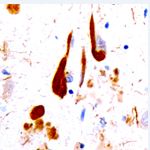

TAU Tau-positive neurons (brown) in the hippocampus of a patient with Alzheimer's disease. |